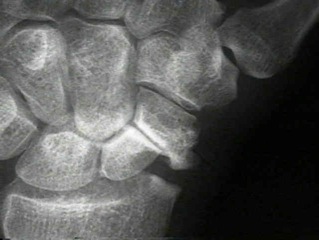

The eight bones in the wrist are arranged into a “proximal row,” furthest from the fingers, and a “distal row,” closest to the fingers. The scaphoid, which technically is in the proximal row, is the most commonly fractured bone of these eight in the wrist. If the scaphoid does not heal, it is called a scaphoid non-union, which ultimately can lead to arthritis.

Patients with scaphoid non-union typically have pain along the thumb side of the wrist and a loss of motion. Some non-unions are those that did not heal despite treatment. Most are diagnosed in people who fell onto an outstretched hand and were not treated initially. X-rays are used to confirm these non-unions and to decide what the right treatment is. A non-union that has not progressed to arthritis might be “fixable,” and a CT scan can help show what the bone looks like.